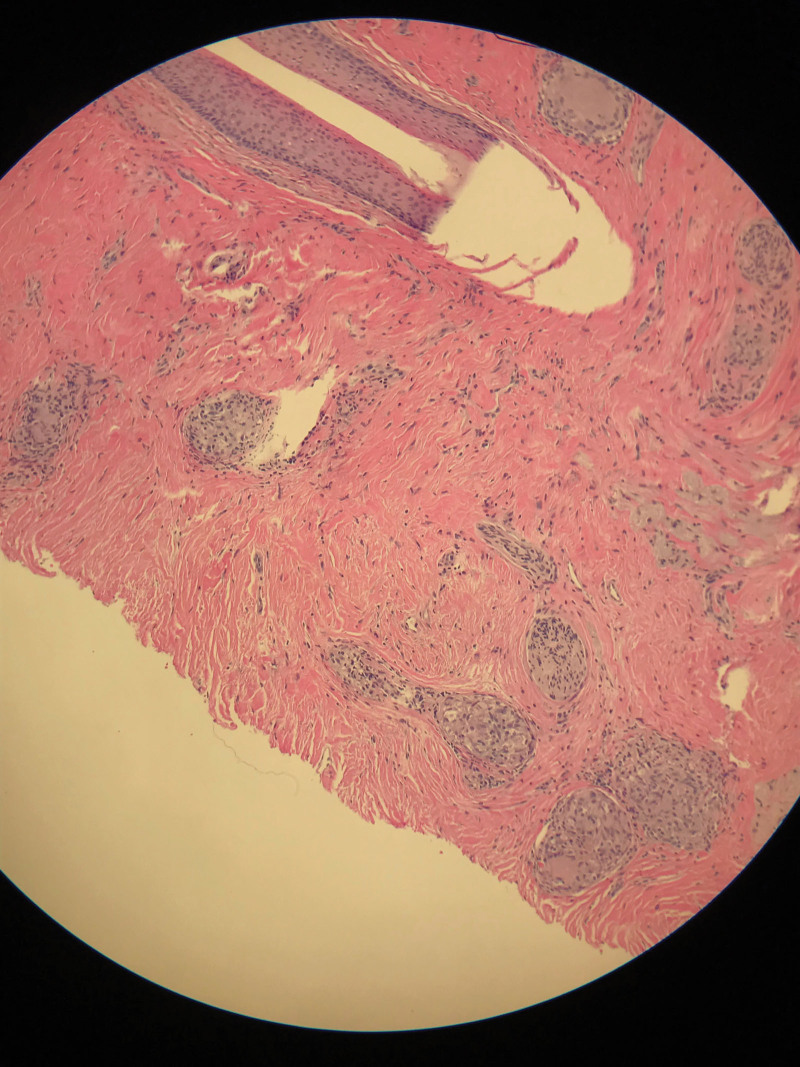

Abstract Image